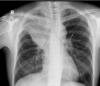

que patrón pulmonar es

A

consolidación